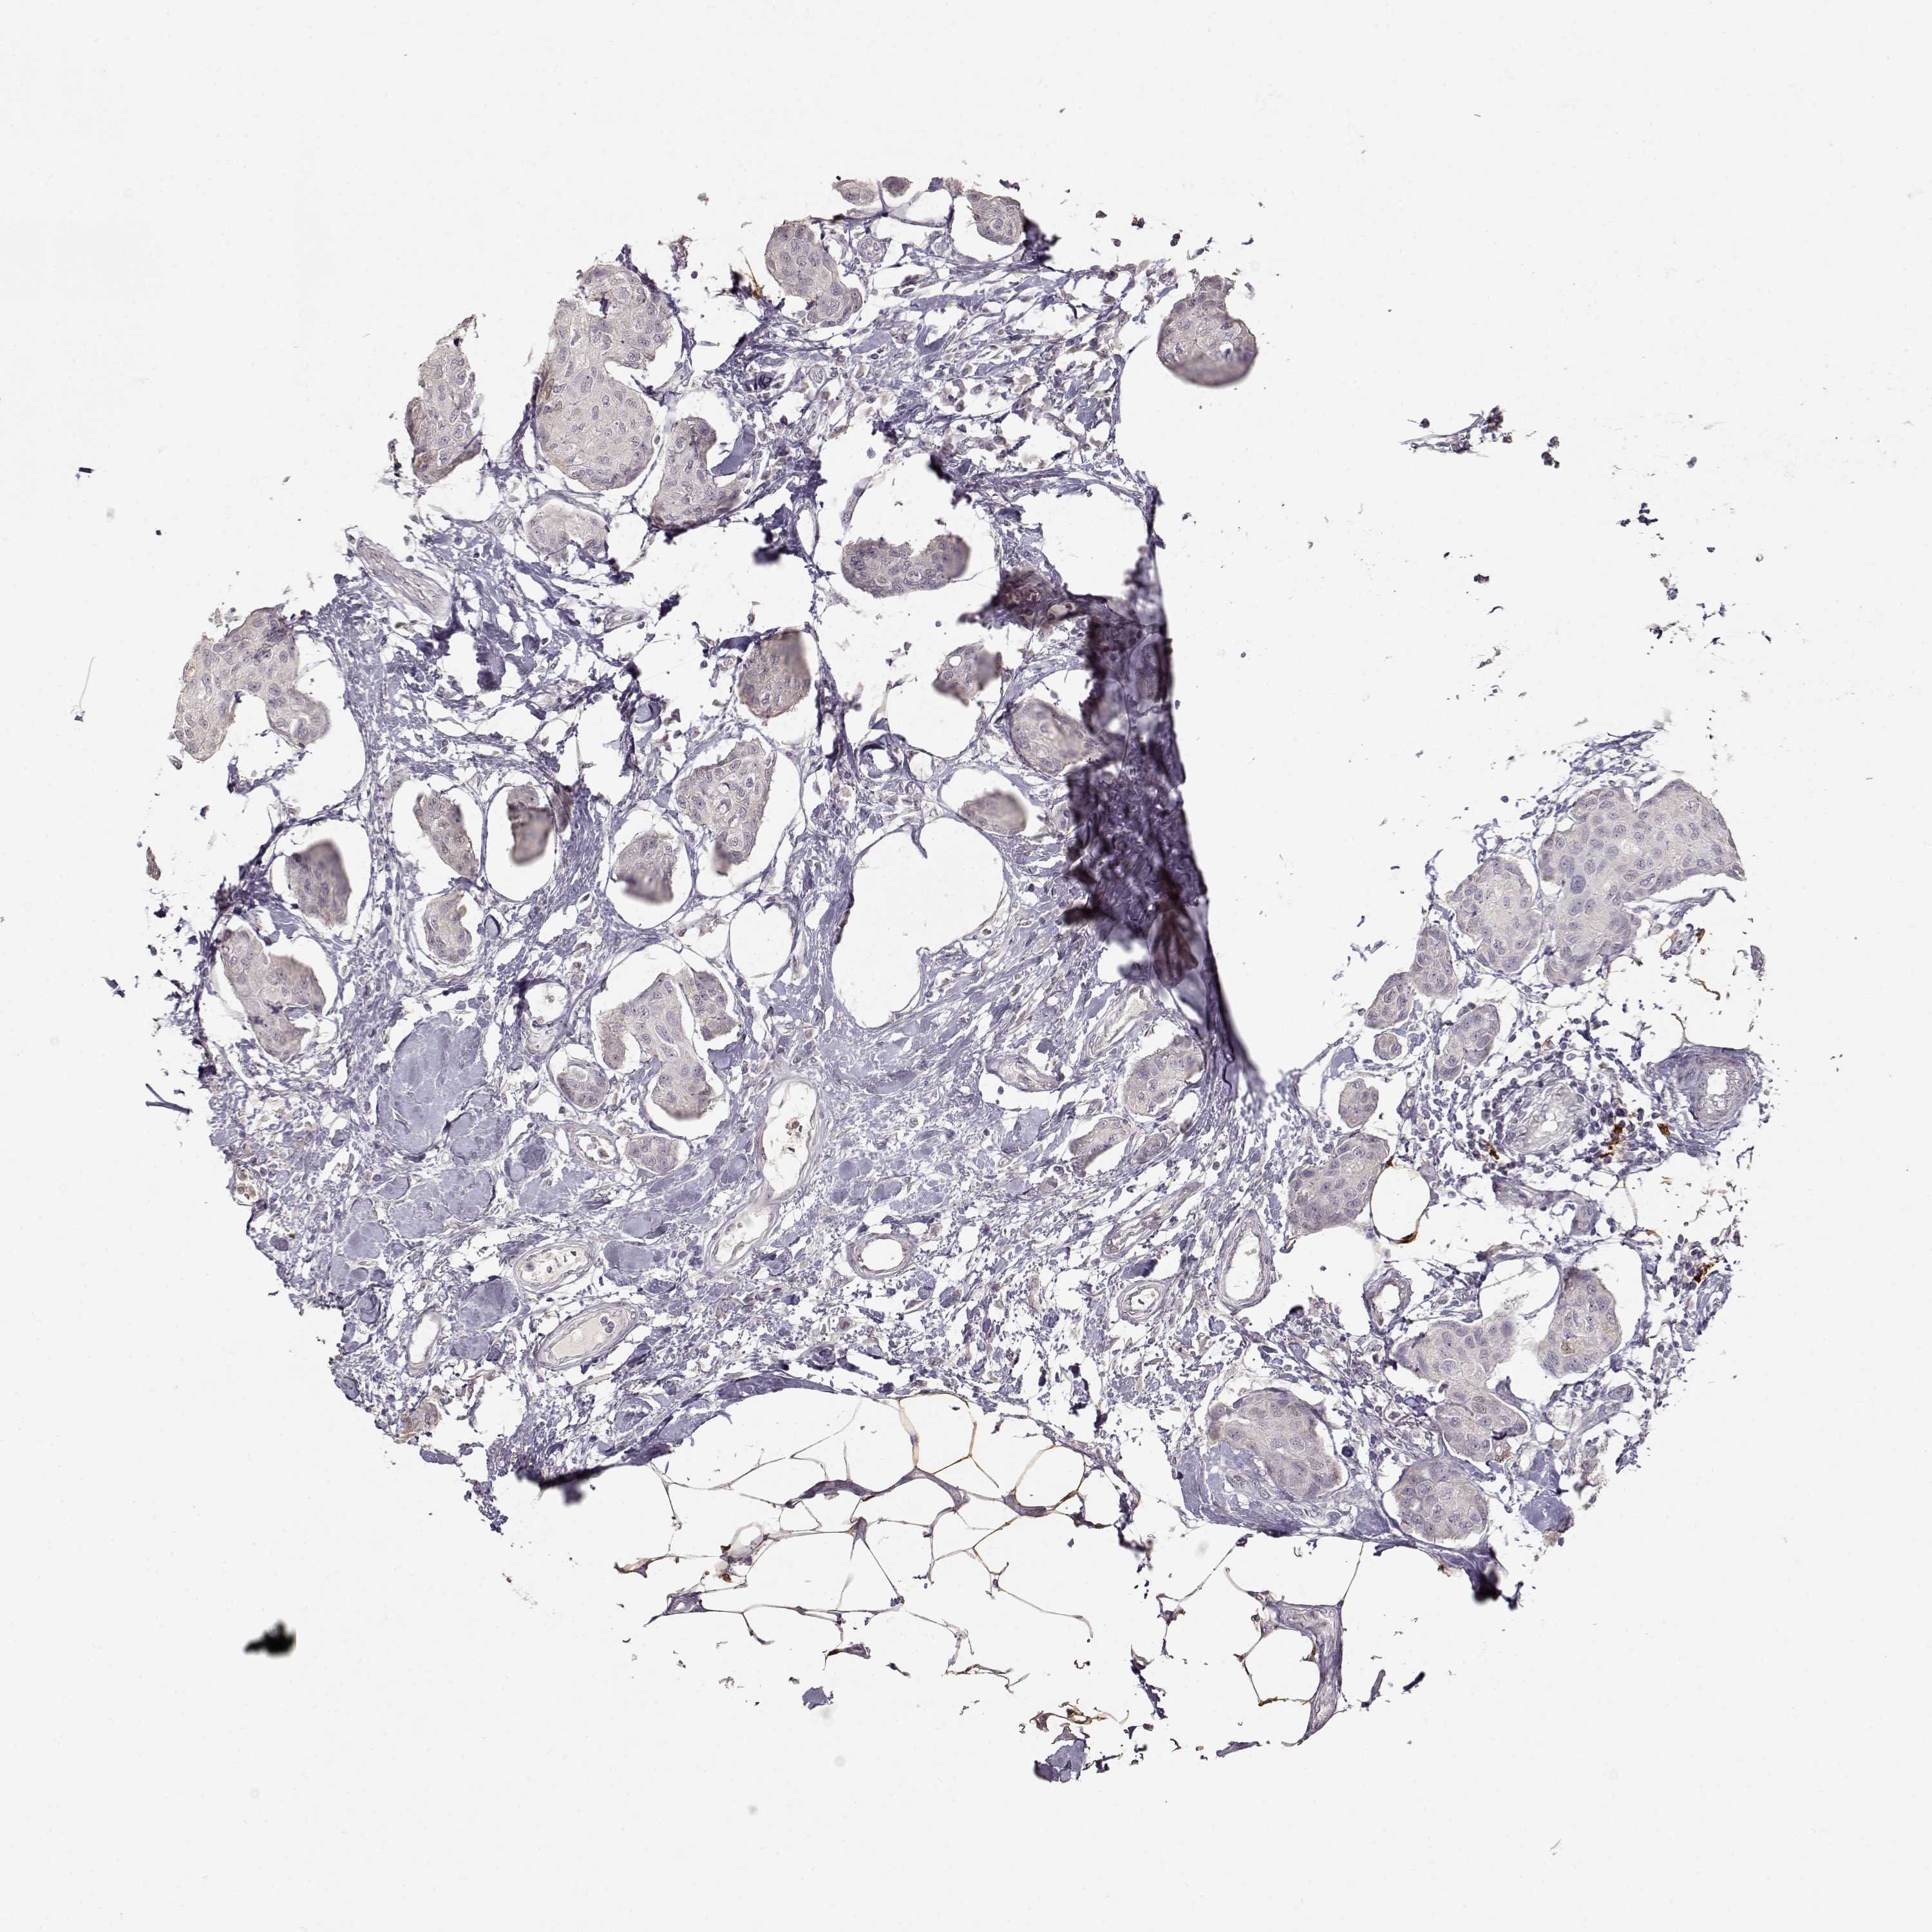

CANCER BREAST CANCER Show tissue menu

BRCA TCGA BRCA VALIDATION PROTEIN EXPRESSION